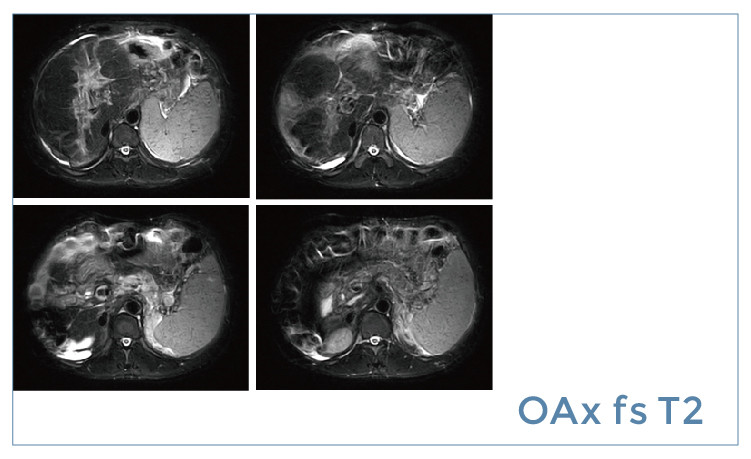

【朗润影像档案】20190621磁共振影像病例结果讨论

【朗润影像档案】磁共振影像病例分享(编号20190621)